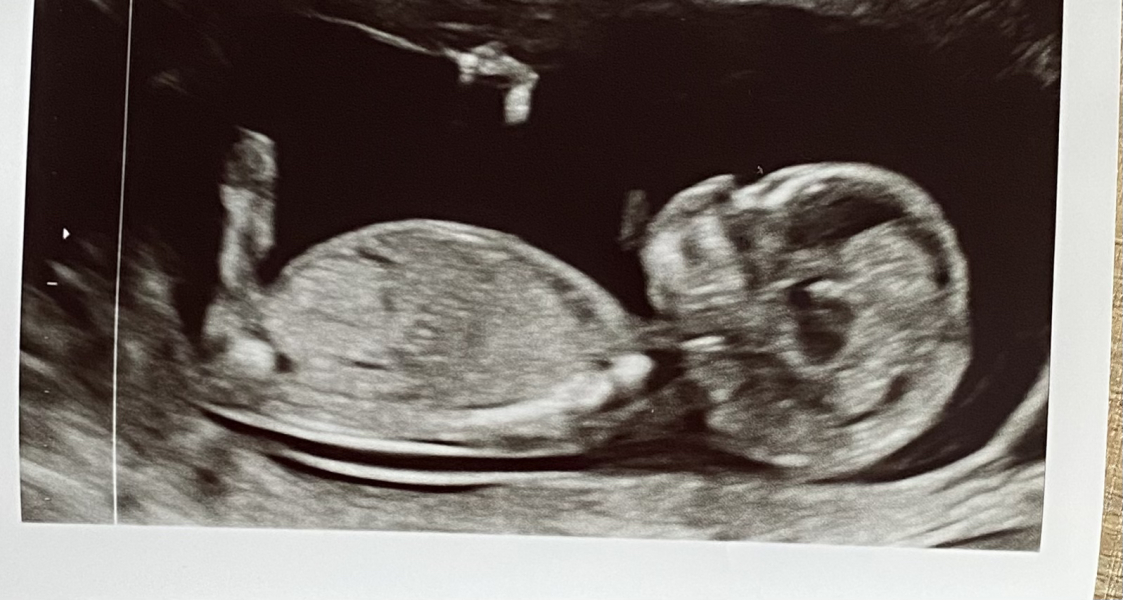

Hi ladies - another scan to add into the mix. Loving seeing everyone’s. I’m 11 and 3, and had NIPT yesterday which included a scan. Laughing at my wee one’s nose. Was assured by the sonographer that it’s the nasal bone but gave us a good laugh!! Got NHS scan at 13 weeks so yet more waiting! Happy weekend to all x

@Sydney1988 that’s a lovely scan 🥰 baby got his feet stretched out, waiting for the time to start kicking mom 😂